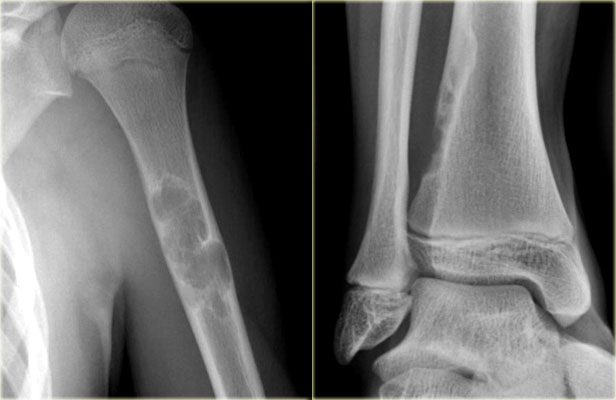

Study the images and then continue reading.

The findings are:

• Pathognomonic triad of bone expansion, cortical thickening and trabecular bone thickening.

• This is the mixed lytic and sclerotic phase of Paget.

• Positive bone scan.

Here we see broadening of the ulna shaft is seen with a mixed lytic-sclerotic appearance and coarse trabeculation.

Differential diagnosis based on the radiograph:

1. Paget's disease

2. Fibrous dysplasia

The intense uptake of the tracer on the bone scintigraphy makes the diagnosis of Paget's disease the most likely.